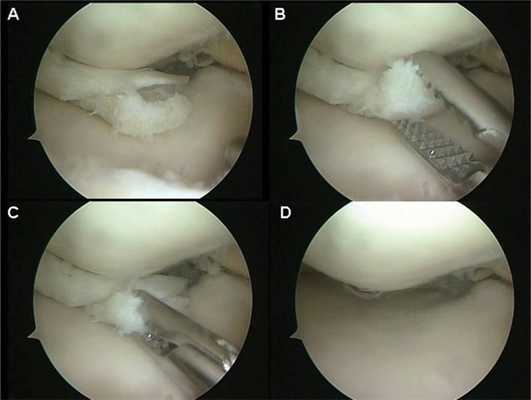

• Артроскопическое формирование блюдцеобразного углубления в мениске для резекции дискоидной центральной части мениска у взрослых с клинической картиной

• Восстановление/резекция разрыва

При бессимптомном течении лечебные мероприятия не требуются. При наличии клинической симптоматики показано хирургическое вмешательство. Операции проводятся с использованием артроскопического оборудования. В зависимости от характера патологии возможны:

- Резекция мениска. Удаление излишков тканей и придание дискоидному мениску нормальной анатомической формы является оптимальным вариантом при отсутствии грубых поражений хрящевой прокладки, поскольку позволяет сохранить ее амортизационную функцию. При гипермобильном типе дополнительно осуществляют подшивание заднего рога к суставной капсуле.

- Тотальная менискэктомия. Исключает риск последующих разрывов измененной хрящевой ткани, но влечет за собой утрату конгруэнтности суставных поверхностей, постоянную перегрузку сустава. Полное иссечение обеспечивает худшие отдаленные результаты, поэтому применяется преимущественно при тяжелых разрывах.

- Артроскопия коленного сустава. Назначается при неоднозначных результатах МРТ или на этапе подготовки к хирургическому вмешательству. Выявляет необычно большую площадь мениска, при травматических повреждениях обнаруживает разрывы.